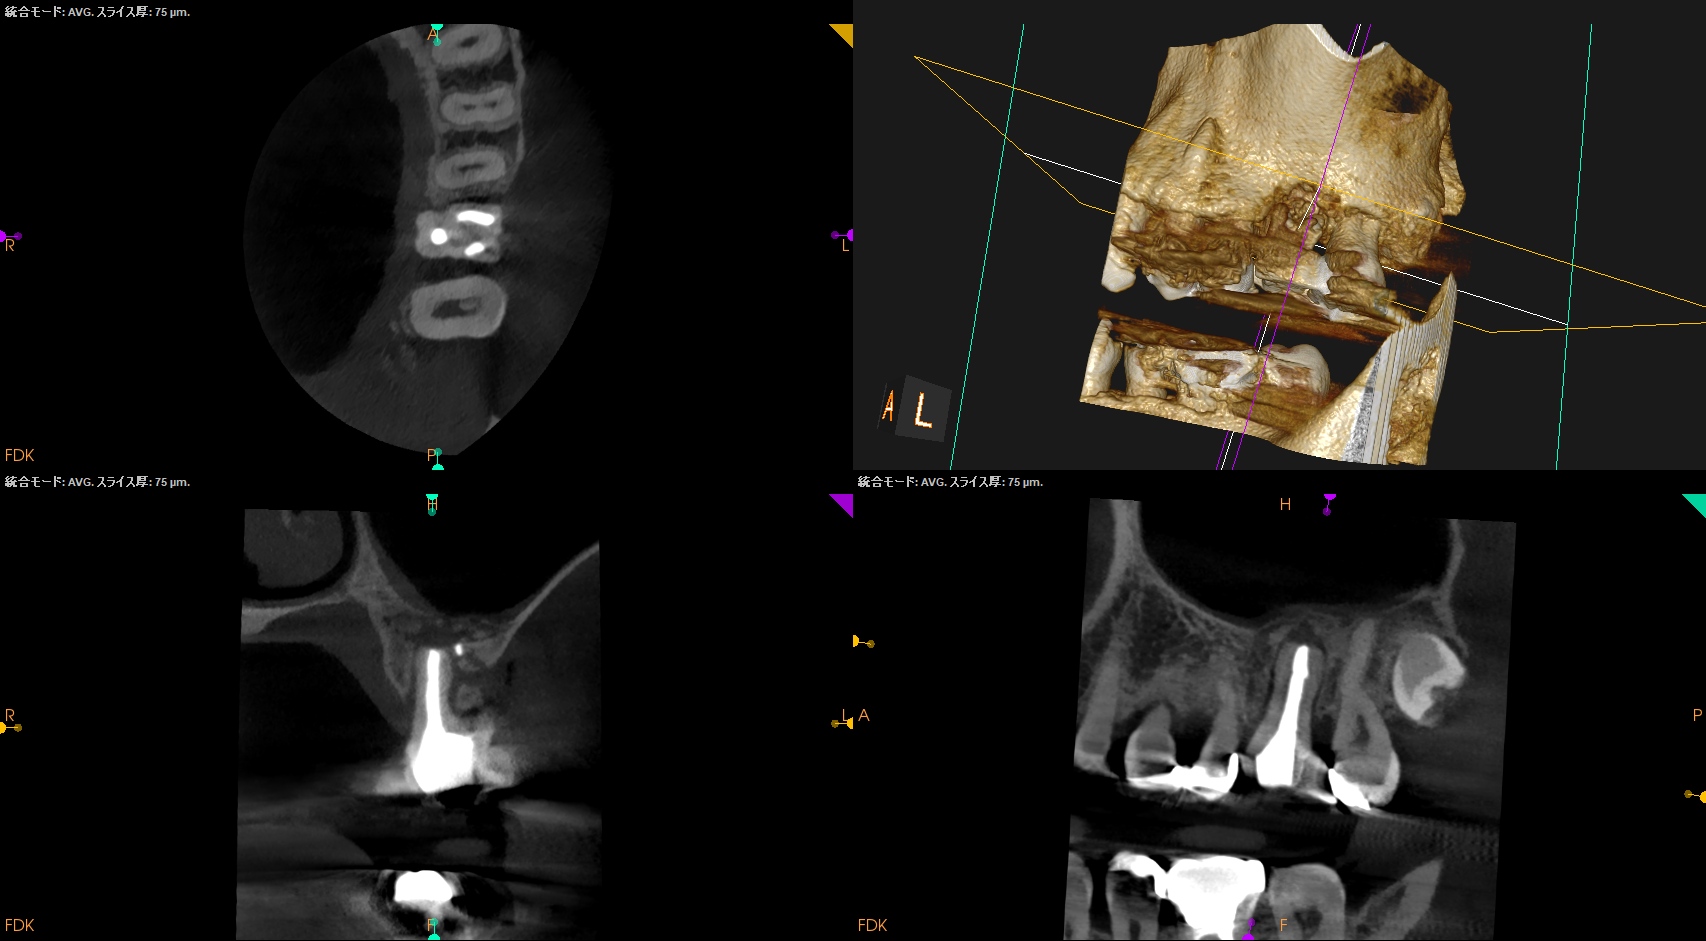

#14 Intentional Replantation 1yr recall(2025.6.6)

臨床症状は消えたが…

MB

DB

P

上顎洞炎は治癒し、Pの歯槽骨はかなり回復したがMB,DBは口腔内に歯根が出てしまっている。

つまりここがエンドポイントになるだろう。